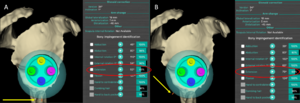

From a clinical perspective lengthening of the arm and humerus, distalization angle, acromio-prosthesis distance (Figures) have been used as surrogates for deltoid tension since they intuitively correlate with deltoid tension and they have been correlated with functional outcome and risk of postoperative instability.[29][30][28] Most of these factors nowadays can easily be evaluated thank to navigation software.[31][32]

It is important to understand the differences between humeral or glenoid lateralization. These factors can be used to predict range of motion and vary based on prosthesis and technical factors. Humeral lateralization is defined as the distance from the center of the polyethylene cup, and the lateral part of the greater tuberosity (Figure). It can be estimated by the lateralization shoulder angle (Figure).

3D distances corresponded to the radius of spheres. Offset of the sphere were centered on the center of the polyethylene cup (pivot point) and of the bony glenoid center (GC) for humeral (A) and global offset (B), respectively, and included the lateral part of the greater tuberosity.

Postero-inferior eccentricity improves extension. A) Inferior eccentricity alone (yellow arrow) allows 52 degrees of extension. B) 40 degrees of postero-inferior eccentricity (yellow arrow) improves extension to 73 degrees.